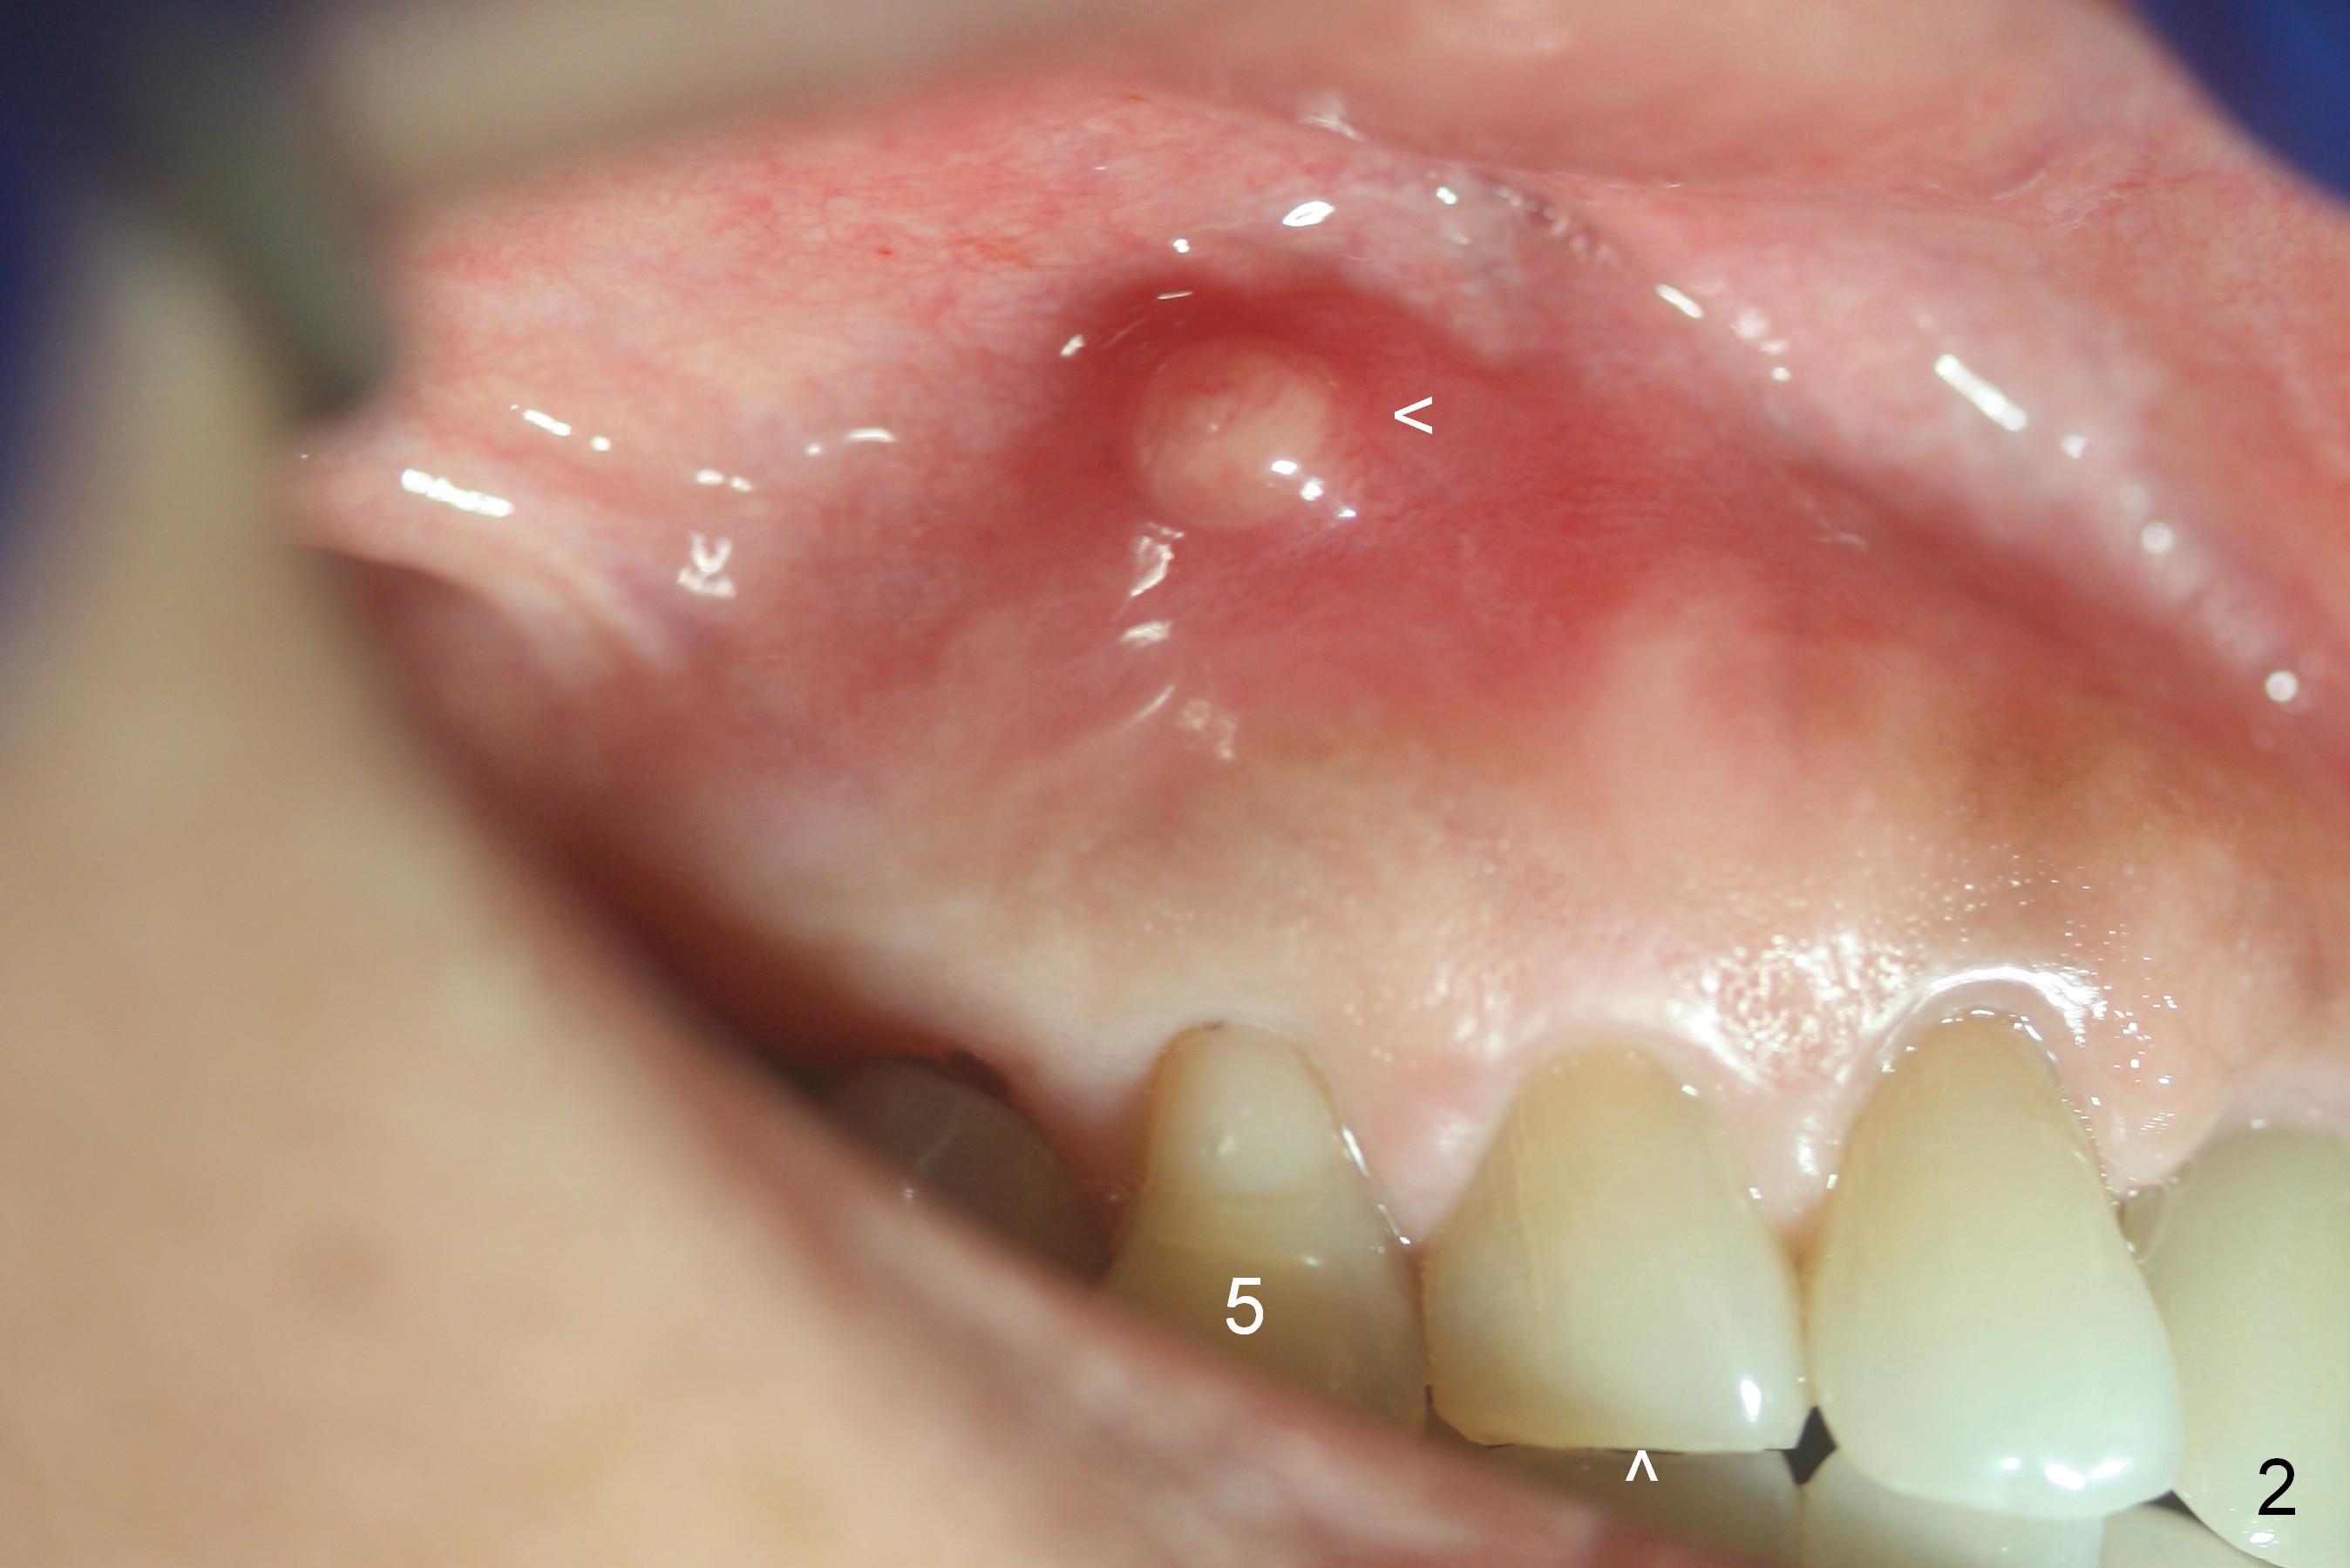

A 72-year-old lady is a bruxer with palatal subgingival fracture of the upper right 1st premolar (Fig.1) with a fistula/periapical radiolucency (Fig.2,3 <).  She insists on saving the tooth, since it is asymptomatic.  Bruxism must be severe, as the canine (Fig.2 ^) is shorter than the lateral incisor.  She has history of #8 fracture and loosening of implant crown at #14.